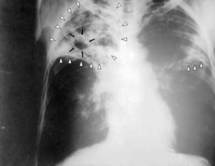

LERAL.NET Le lancement du Projet TB Global Fund R10 de Plan Sénégal a été effectué, ce matin, à Dakar. D’un coût de 2(deux) milliards et poussière de nos francs, cette croisade contre la plus démocratique des maladies connues dans le monde, entend ériger au rang de ses priorités l’approche communautaire

Selon le Docteur Boubacar Gueye, représentant Madame le Ministre de la Santé, de l’Hygiène Publique et de la Prévention Médicale : « Au Sénégal, la tuberculose demeure un problème de santé publique d’une importance accrue. Selon les dernières estimations de l’OMS, les nouveaux cas de tuberculose survenus dans la population sénégalaise s’élevaient à 36 000 durant l’année 2010 soit de 288 nouveaux cas pour 100000. Les mêmes estimations faisaient état de 62 décès pour 100000 habitants liés à la tuberculose la même année .D’où l’urgence d’agir. Cependant, on ne peut rien faire sans les populations. C’est pourquoi, nous préconisons l’approche communautaire pour venir à bout de cette maladie», a-t-il souligné. Et le docteur Momar Talla Mbodj, chef dudit projet à Plan Sénégal de rajouter : « Il est inacceptable qu’une maladie curable comme la tuberculose continue de faire des ravages qui détiennent sensiblement sur notre économie. Nous allons venir en complémentarité aux structures sanitaires du Sénégal. Quelque 5713 relais seront déployés. Ces derniers vont chercher les potentiels tuberculeux pour, ensuite, les référer dans une structure de santé» .Ce projet qui est accès sur les résultats et d’une durée de cinq(5) ans va faire un focus sur les zones à forte concentration humaine comme Dakar, Thiès, Mbour, Diourbel et Ziguinchor mais aussi sur les régions frontalières.